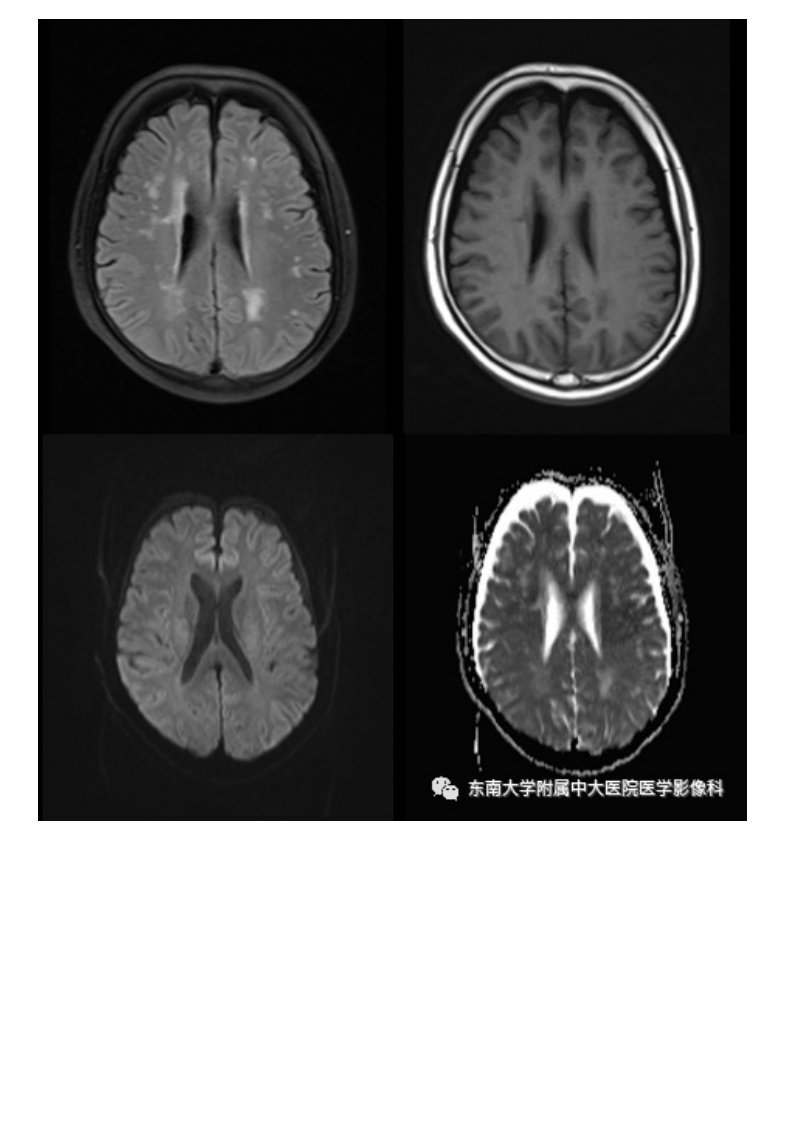

20201216_2【晨读结果公布】2020.12.15神经系统疾病——脑卒中模拟病.pdf